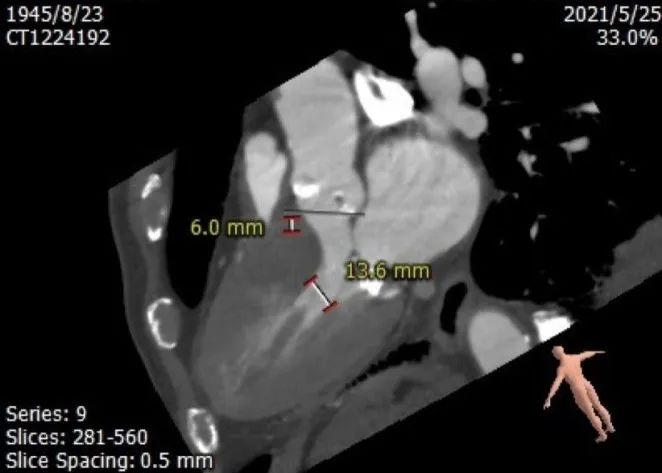

心室情况:

左室前后径28.7mm,左室最小径13.6mm,瓣环下6mm存在心肌膨出,

CT数据显示该患者为三叶三窦式主动脉瓣。

1. 主动脉瓣瓣环周长70.6mm,平均周长径 22.5mm,SOV:28.5mm*28.7mm*29.9mm,瓣叶增厚,瓣上钙化明显。

钙化评估:

中度钙化,HU850积分472m㎡,RCC钙化最严重,其次为LCC、NCC。

①患者主动脉瓣钙化较重,瓣环下6mm存在心肌膨出,瓣膜植入后可能存在偏移,左室传导阻滞风险高,应小心释放,释放定位应选择瓣环下0-4mm处。